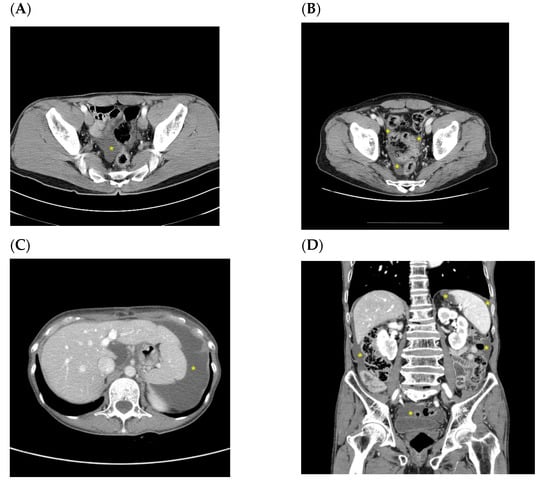

| Patients with ascites presumed to be benign before confirmation of recurrence (n = 8) | ||||||||

| Pt 1 | 65/M | PG | T3N3a | small pelvic cavity | Simultaneous with recurrence | T colon (increased ascites in the pelvic cavity) | 44.4 | 8.1 |

| Pt 2 | 53/F | TG | T4bN3b | small pelvic cavity | Simultaneous with recurrence | Peritoneum (increased ascites, peritoneal thickening, bowel obstruction, and Krukenberg tumors) | 18.2 | 13.2 |

| Pt 3 | 40/F | TG | T4aN3a | small pelvic cavity | Simultaneous with recurrence | Peritoneum (nodularity and increased ascites) | 73.2 | 70.3 |

| Pt 4 | 59/F | TG | T4aN3a | small pelvic cavity | Simultaneous with recurrence | Peritoneum (increased ascites and peritoneal thickening) | 25.2 | 21.7 |

| Pt 5 | 39/F | TG | T3N3b | small pelvic cavity | Simultaneous with recurrence | Peritoneum (Krukenberg tumors, nodularity, and increased ascites) | 12.1 | 9 |

| Pt 6 | 57/F | TG | T3N3a | small pelvic cavity | Simultaneous with recurrence | Peritoneum (bowel obstruction and increased ascites) | 9.8 | 4.4 |

| Pt 7 | 61/F | TG | T3N1 | small pelvic cavity | Simultaneous with recurrence | Peritoneum (increased ascites, T colon, and mesentery LNs) | 29.6 | 26 |

| Pt 8 | 68/F | PG | T4aN2 | small pelvic cavity | Simultaneous with recurrence | Peritoneum (increased ascites and peritoneal thickening) | 11.7 | 5.3 |